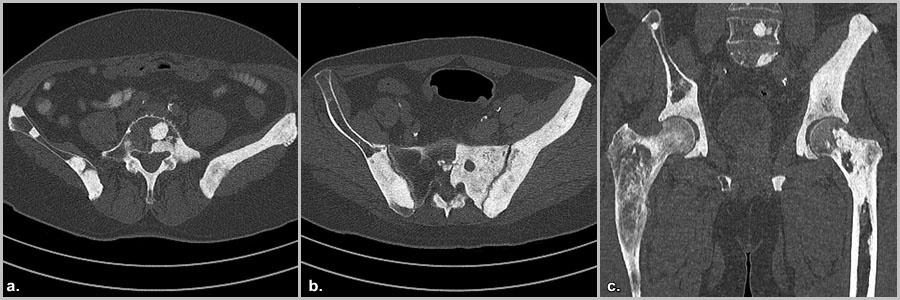

Можно ли выявить метастазы в кости на ранней стадии?

Ранняя диагностика сложна, но возможна. Современные методы:

1. Сцинтиграфия костей (остеосцинтиграфия)

«Золотой стандарт» скрининга. Выявляет аномальные участки накопления радиофармпрепарата.

Недостаток: Низкая специфичность — воспаление или травма тоже дают сигнал.